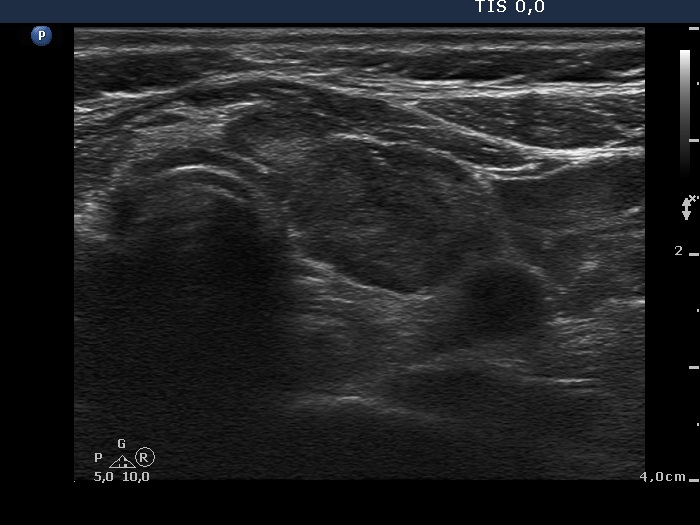

Ultrasonography: There was no parenchyma according to the right lobe, while there was a relatively large thyroid tissue in the left lobe. The latter displayed increased vascularization.

Ultrasonography: The pattern remained unchanged.

Ultrasonography: unchanged.